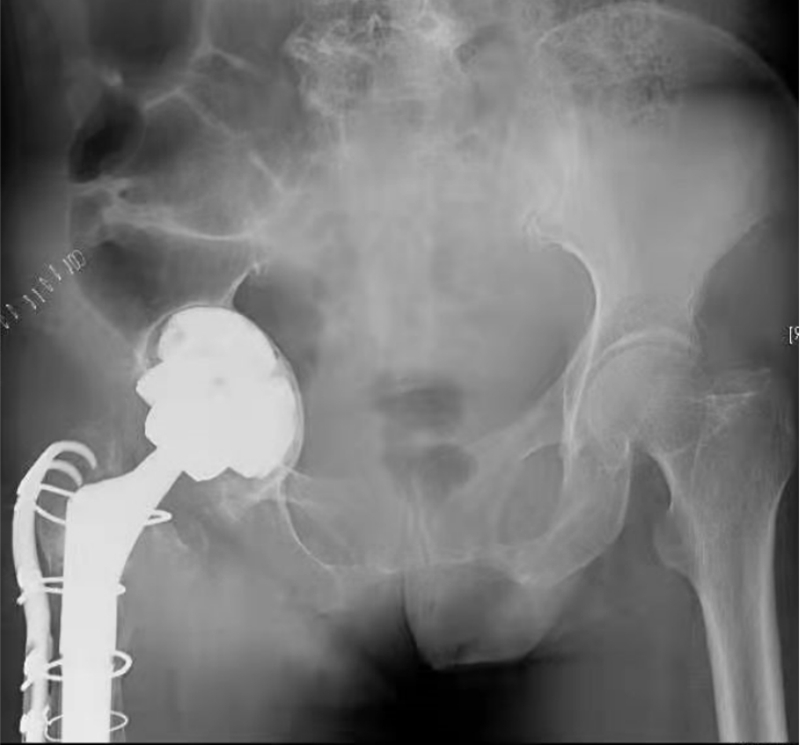

患者女性,7岁,右侧全髋关节置换术后16年,髋臼侧假体松动移位,合并严重的骨缺损和右下肢短缩(图5),诊断为“右髋关节置换术后假体无菌性松动”。手术前通过对CT影像进行降噪、分割、骨缺损范围识别后,对骨缺损修复和髋臼假体位置进行3D规划,手术由田华主任和李锋教授共同完成(图6)。

术中,VTS导航系统不仅可以追踪髋臼磨锉、假体位置和前倾角/外展角等关键角度信息,还可以对补块位置进行示踪(图7),将补块和假体安放的位置和角度精确到1mm和1°,从而最大程度地避免了人工操作的误差和对重要生理结构的副损伤,大大提高了骨缺损修复的精准性和手术操作的安全性。术后患者恢复良好,影像学显示补块及假体位置满意(图8),术后第二天即可下地活动。

图5 患者术前X光片,右髋置换术后,现假体松动、严重髋臼侧骨缺损

图8 患者术后X光片,补块和假体位置满意,精准实现了术前规划